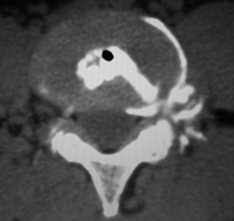

对脊椎的骨・关节的状态进行断层扫描形成3D立体图像对病变处精确诊断的必要检查。还可对脊柱棘突,有无脊柱分离症,椎间盘钙化进行详细的诊查。还可诊查有无大动脉瘤,内脏的病变和腰痛的原因等等。 |

CT 3D立体图像

| 椎间盘造影 | 检查外侧突出的重要检查项目。在椎间盘处注入造影剂再进行CT扫描 |

椎间盘造影